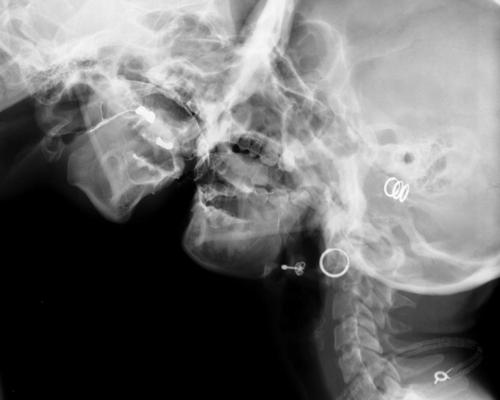

[…] Cuando el artista belga Wim Delvoye realiza imágenes por rayos X de un beso o de actos sexuales, imágenes X por medio de rayos X, no hace otra cosa que apropiarse estéticamente de técnicas científicas a veces de punta, reintroduce la «skiagrafía», excluida antiguamente por la filosofía, y, en la ciencia, lo concerniente al acto sexual, que ella excluye.

Podríamos evocar dos imágenes radiográficas de Wim Delvoye. Estas imágenes tomadas por rayos X, clasificables en la góndola de las imágenes X, poseen una fuerza de verdad extrema. Sin embargo, no donde uno cree, no donde uno ve. Al mostrar un beso o una felación, son para verlas, desde luego, como toda imagen, pero ellas muestran lo que no se ve a simple vista, el interior de los cuerpos en actividad. Ellas nos sitúan en un tiempo posterior al cine pornográfico. El valor del surgimiento del cine pornográfico, si ese valor existe, es en el fondo, haber mostrado algo, una parte de la anatomía que el cine jamás había mostrado, los órganos sexuales en actividad. Las imágenes de rayos X, al ir más allá de la anatomía, van más lejos: van al sexo bajo la piel. Por otra parte, si bien tales imágenes cumplen el sueño de la cámara pornográfica de mostrar desde lo más cerca posible, esto no produce exactamente una mayor excitación sexual. En verdad, las imágenes de Wim Delvoye tienden a mostrar una cosa que no se había visto nunca: cómo funciona el sexo. Sin embargo, debería decirse más bien que lo que estas imágenes muestran, es que no se lo ve. Más aún, que lo normal es que no se lo vea.

[…] Para más exactitud, yo diría que estas imágenes de rayos X, que es posible reunir con el dibujo anatómico de Leonardo en el que se representa el corte de un coito muestran sobre todo que hay algo que no se puede ver: cómo funciona el amor, cuál sería el secreto del sexo. Tal es su dimensión crítica. Ellas se dirigen también a los médicos y a todos para decir que la búsqueda de la transparencia del cuerpo es una fantasía, porque hay algo que jamás se podrá ver ni saber, y por lo tanto dominar: la relación sexual. Pueden ustedes radiografiar el cuerpo, autopsiar el cuerpo, volverlo todo lo transparente que quieran, pero jamás verán con sus ojos el secreto de la relación sexual; o mejor dicho, jamás verán la única verdad que hace saltar los ojos: que no hay nada que ver, que no hay secreto. Esto es lo que, al fin de cuentas, resiste definitivamente a la voluntad del amo de que «eso funcione».